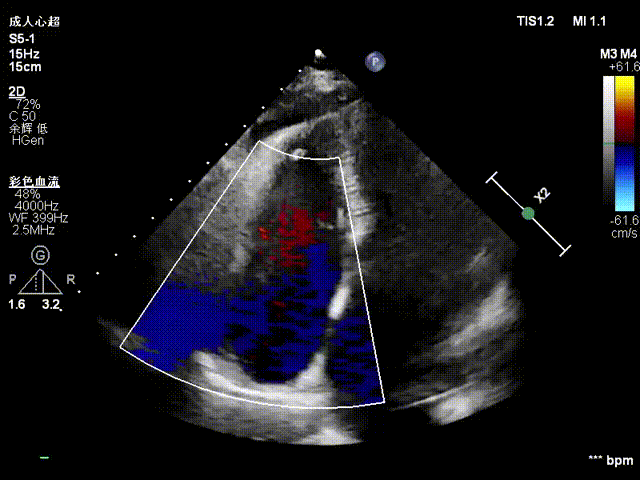

Echocardiographic Findings:Severe tricuspid regurgitation (4+; average vena contracta width, 12 mm). The regurgitation was predominantly anteroseptal and central, with a small posteroseptal component. During systole, the anterior and septal leaflets protruded slightly into the right atrium, with a protrusion height of 2.6 mm. A 6 mm gap was observed at the anteroseptal and central regions. Tricuspid annular dilatation was present (mean annular diameter, 40 mm), with a prominent gap at the anteroseptal region.

Preoperative TTE: 4-chamber view regurgitation